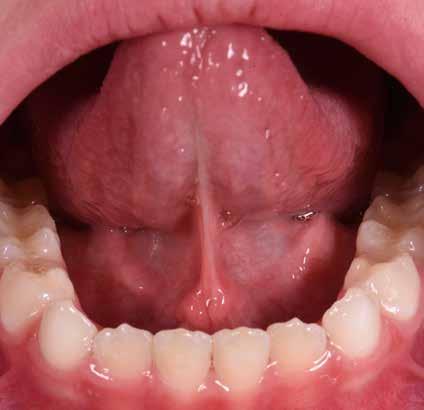

Lingua

Nel corso del primo esame obiettivo vengono valutati forma, colore e confgurazione della lingua Figg. 14-15

La lingua può essere stretta, lunga o larga, senza che da tali riscontri si possano trarre conclusioni sulle dimensioni relative della lingua stessa. Le modifcazioni della posizione e della mobilità della lingua sono spesso associate ad aderenze del frenulo linguale Fig. 16 Le impronte dei contorni dentali presenti sul margine della lingua indicano una discrepanza tra la larghezza dell’arcata dentale e la larghezza della lingua stessa. In questi casi la terapia ortognatodontica non deve assolutamente ridurre ulteriormente il cavo orale (come, ad esempio avviene con le estrazioni dei premolari) ma piuttosto aumentare lo spazio a disposizione per favorirne il corretto funzionamento (Ferrante 1996). Una valutazione approssimativa delle dimensioni della lingua in rapporto alle dimensioni della cavità orale può essere effettuata basandosi sulla teleradiografa. La lingua rappresenta il motore della terapia elastodontica; infatti, essa è un volume tridimensionale che assume un ruolo morfogenetico in fase di crescita, un ruolo equilibratore in fase intermedia ed un ruolo compensatore in fase adulta (Stefanelli 2003).

14,15 _

16 _

17,18 _

Forme diverse della lingua: spanciata ed a punta.

Frenulo linguale corto.

Frenuli labiali superiori.